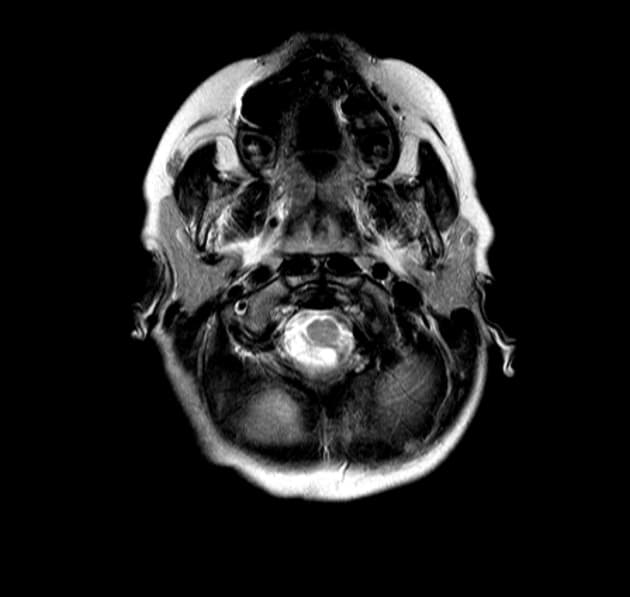

Axial T2

Hình ảnh ghi nhận sự phì đại đơn bên ở bán cầu tiểu não trái, đặc biệt là vùng neocerebellum, với bằng chứng giảm tín hiệu trên xung T1 và tăng tín hiệu trên xung T2 tại phân đoạn bị ảnh hưởng. Các nếp gấp tiểu não (folia) cùng bên xuất hiện phì đại nhẹ, kèm theo biến dạng não thất bốn và lệch thân não sang phải. Có hình ảnh tăng quang màng não mềm (leptomeningeal enhancement) đi kèm. Cả hai não thất bên, não thất ba và sừng thái dương đều giãn rộng. Không thấy hình ảnh (no evidence of) bất thường trong nhu mô não.